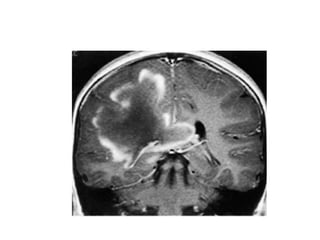

• Schilder type, or myelinoclastic diffuse

• refers to an entity consisting of extensive, confluent,

asymmetric demyelination of both cerebral hemispheres with

involvement of the brainstem and cerebellum. It is usually

• seen in children presenting with seizures, signs of pyramidal

tract involvement, ataxia, and psychiatric symptomatology.

• Adult cases have aso been described .

• Typically, there is a rapid progression of disease over the

course of 1 to 2 years, but the demyelinating process may be

fulminant se..

• Concentric sclerosis (Balò type)

• IT is a very rare type of demyelinating disease in which

large regions with alternating zones of demyelinated and

myelinated white matter are found.

• The myelinated regions may reflect remyelination rather

than spared normal myelin.

• This progressive disease is more often found in young

patients and is more common in the Philippines.

• When encountered, Balò concentric sclerosis has a

pathognomonic appearance on both pathology and MR

• Tumefactive MS

• Tumefactive MS is a variant of

Multiple Sclerosis.

• The open-ring enhancement

pattern with low signal T2 ring

and low CBF are all indicative

of demyelination.